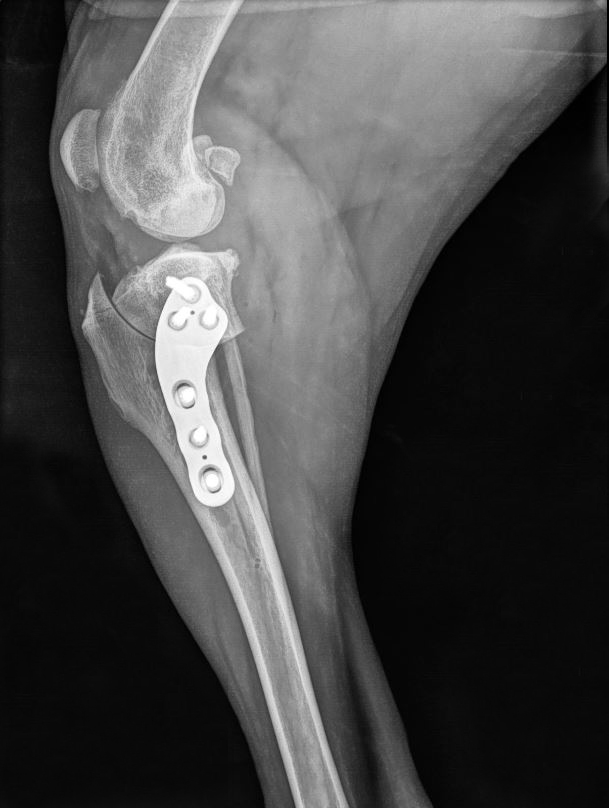

Tibial Plateau Leveling Osteotomy (TPLO) is a surgical procedure commonly used to treat cranial cruciate ligament (CCL) ruptures in small animals, particularly dogs. The cranial cruciate ligament is analogous to the anterior cruciate ligament (ACL) in humans and is responsible for stabilizing the knee joint.

When the cranial cruciate ligament ruptures, it leads to instability in the knee joint, causing pain, lameness, and eventually arthritis if left untreated. TPLO is designed to address this instability by altering the mechanics of the knee joint rather than attempting to replace the ligament itself.

One of the standout features of the LeiLOX TPLO System is its multiaxial locking capability, offering unparalleled precision and safety during surgery. The screws can be securely locked in a 90° angle with a 12° deviation in any direction, enabling you to angle the screws away from vital structures with confidence. The robust stardrive screw head ensures firm locking into the plate, minimizing the risk of instability and ensuring long-term success.

Designed with the utmost consideration for anatomical integrity, LeiLOX TPLO plates are contoured to match the natural shape of the bone, facilitating optimal positioning with ease. This anatomical conformity not only enhances surgical efficiency but also minimizes vascular damage to the plated bone segment, promoting faster healing and reduced postoperative complications.

The LeiLOX TPLO System features two precisely designed compression holes that enable exceptionally tight compression of the osteotomy. The presence of two compression holes also allows for more uniform compression across the osteotomy site, as well as making adjustments in compression levels based on the specific needs of each patient. The incorporation of double compression holes in our LeiLOX TPLO Implants enhances stability and support, which is crucial for proper and faster bone healing.